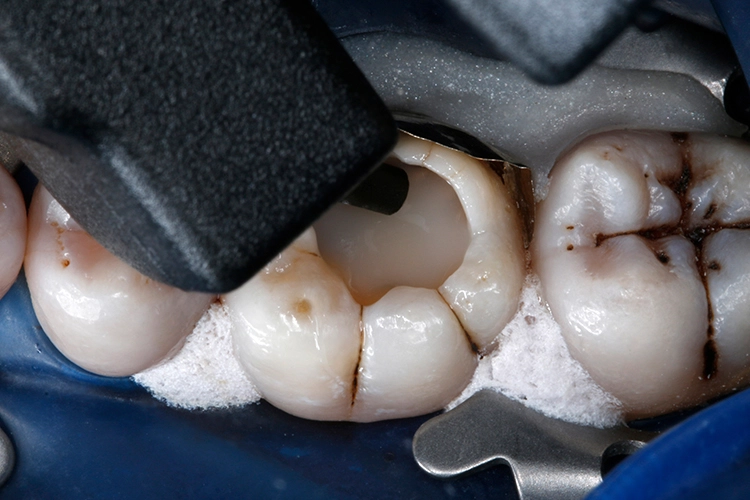

Anschließend wurden sämtliche Kavitätenränder mit einem Feinkorndiamanten nachgearbeitet und finiert. Danach wurden die pulpanahen Kavitätenareale mit einem selbstlimitierenden Polymer-Rosenbohrer (Polybur, Gebr. Brasseler GmbH & Co. KG, Lemgo) substanzschonend exkaviert (Abb. 7), eine Exposition der Pulpa konnte mit diesem Vorgehen der selektiven Exkavation vermieden werden (Abb. 8) [51–55]. Das pulpanahe Dentin im Zentrum der Kavität wurde mit einer dünnen Schicht röntgenopaker Calciumhydroxidpaste auf wässriger Basis (Calcicur, VOCO) indirekt überkappt (Abb. 9). Das Calciumhydroxidpräparat wurde mit einer partiellen Unterfüllung aus lichthärtendem kunststoffmodifiziertem Glasionomerzement (Ionoseal, VOCO) abgedeckt (Abb. 10).